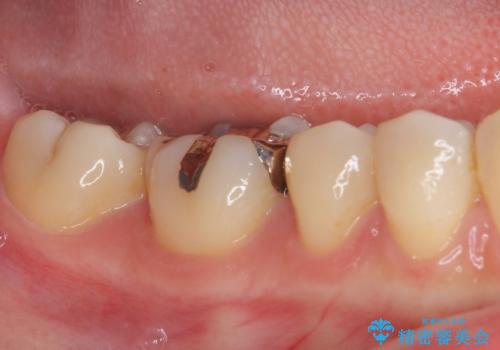

- 下の奥歯(右下7・左下7)にあって目立ってしまう銀歯を白くしたいとのことで来院された患者様です。

セラミックインレーにて修復治療を行うこととしました。